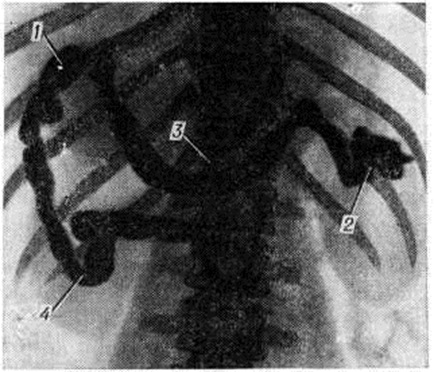

Патологическая анатомия. Патологоанатомические изменения при внутрипечёночной и надпечёночной форме Портальная гипертензия обусловлены вызвавшими их заболеваниями (смотри полный свод знаний: Киари болезнь, Циррозы печени). При внепечёночной Портальная гипертензия печень может быть уменьшена в размерах, без признаков цирроза, отмечается лишь некоторый фиброз портальных сосудов. Селезёнка увеличена, нередко с постинфарктными рубцами и массивными сращениями с окружающими тканями. При гистологический исследовании селезёнки определяется в той или иной степени фиброадения её пульпы. Сосуды портальной системы дистальнее препятствия расширены, деформированы с неравномерно склерозированными стенками (рисунок 1). Расширенные коронарная вена желудка (левая желудочная вена) и вены подслизистого слоя пищевода выбухают в просвет, иногда на некотором протяжении стенки их истончены. Основные стволы портальной системы могут быть полностью облитерированы с образованием густой сети расширенных, деформированных сосудов брыжейки тонкой кишки, области селезёнки и желудка.

Рис. 1. | ||